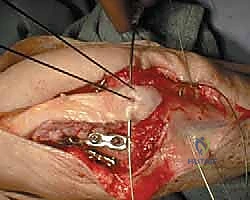

TECH FIG 1 • A. A lateral radiograph with the arm in plaster shows a transverse, noncomminuted fracture of the olecranon. B. An open reduction is held with a fracture reduction forceps.

TECH FIG 1 • A. A lateral radiograph with the arm in plaster shows a transverse, noncomminuted fracture of the olecranon. B. An open reduction is held with a fracture reduction forceps. (continued)